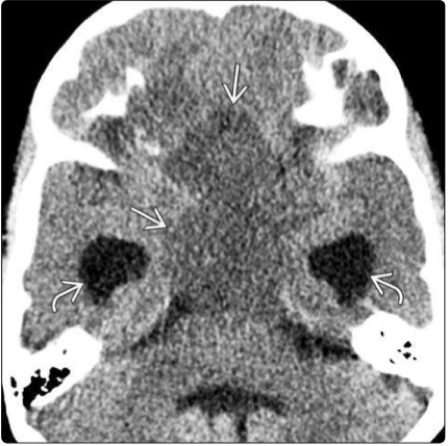

小脑,人类大脑的一个重要组成部分,位于大脑半球后方,覆盖在脑桥及延髓之上,横跨在中脑和延髓之间。小脑是重要的运动调节中枢,包括维持身体平...

与成人中枢神经系统中的许多恶性肿瘤相比,儿童的脑部恶性病变的治疗、治疗反应和未来前景具有着广阔的前景。在过去的5年中,国际神经外科对包括髓...